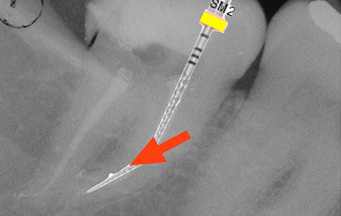

Even if not new in endodontics, the reciprocating motion has been recently applied to specifically designed nickel-titanium (NiTi) instruments. Reciprocation has reduced the risk of fracture due to torsion and to the accumulation of metal fatigue, which are the main shortcoming of rotary NiTi instruments. After 4 years of extensive clinical use, research and teaching of all these instruments, the lecturers will describe and explain the several advantages that are related to the use of this kind of movement. Reciprocating instruments are very easy to be used and taught, the learning curve is extremely short and optimal clinical results can be obtained earlier of other rotary systems. It became very simple, safe and fast to complete successfully even the most difficult clinical cases, while maintaining the maximum clinical standard of a high level practice and drastically reducing possible errors and problems related to the root canal preparation. All these aspects will be extensively and critically analyzed and discussed giving particular attention to the research conducted on the reciprocating instruments on the market and the clinical step by step of these techniques.